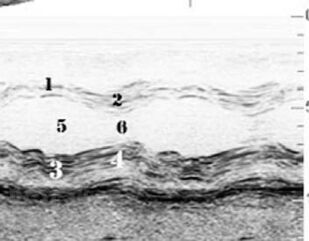

Рассмотрены основные режимы трансторакального эхокардиографического исследования, методика выведения стандартных эхокардиографических позиций, методика основных измерений структурно-функциональных показателей деятельности сердца.